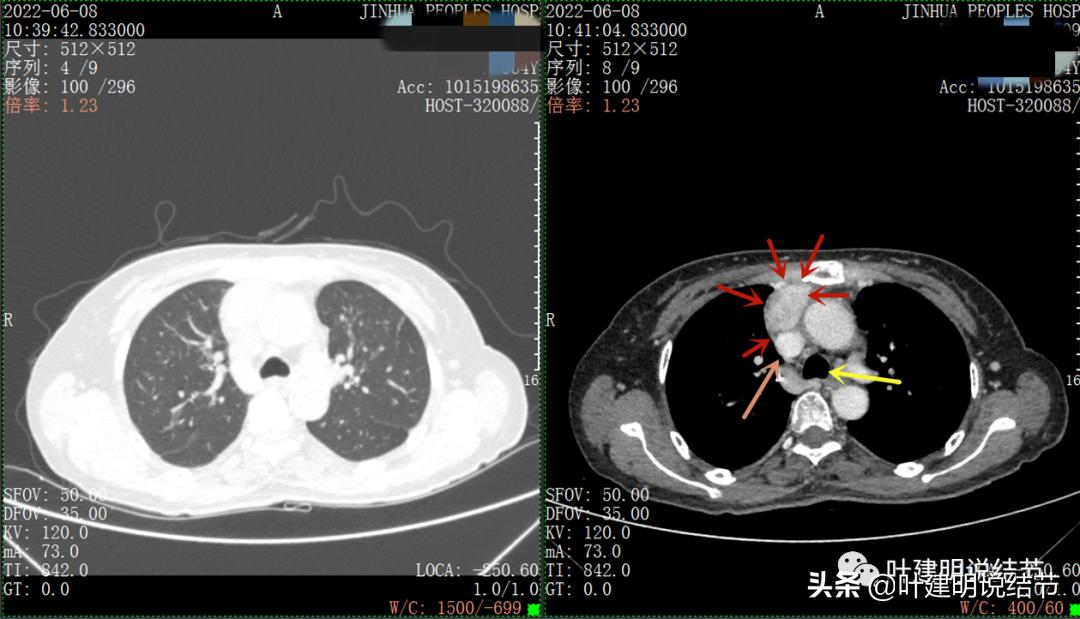

以下图片左侧是肺窗,右侧是纵隔窗。红色箭头示病灶,桔色箭头示无名静脉,黄色箭头示支气管,砖色箭头示上腔静脉,蓝色箭头示主动脉,紫色箭头示肺动脉。

病灶占据前纵隔从上到下全程,多中心,密度不均,对心脏与大血管有压迫,没有明显侵犯

上图示最大横断位达5厘米

纵隔如此巨大的占位,恶性是基本上能肯定的了,到底要考虑淋巴瘤、胸腺瘤、胸腺癌、畸胎瘤或其他恶性肿瘤呢?一般来说,应该是胸腺癌或淋巴瘤可能性为大。再来看看化验检查。